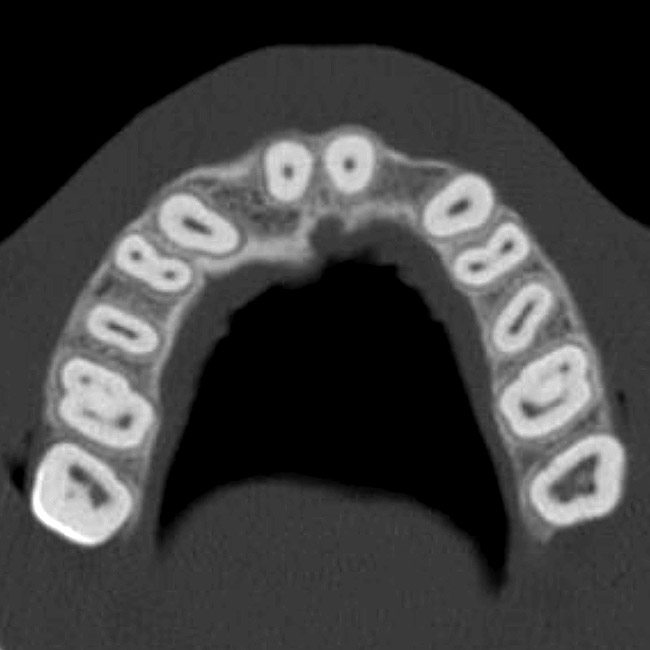

Figure 6a  By slicing the maxilla axially, the images revealed (A) the differing morphology of the central incisors, canines, premolar, and molar roots, and (B) the left simulated implant seen encroaching on the adjacent lamina dura.

Figure 6a

Figure 6b  By slicing the maxilla axially, the images revealed (A) the differing morphology of the central incisors, canines, premolar, and molar roots, and (B) the left simulated implant seen encroaching on the adjacent lamina dura.

Figure 6b

The CT axial views represent an important instrument in gaining a better understanding of anatomical features that can not be determined by any other imaging modality (Figure 6A). When the maxilla is sliced axially at the level where the roots meet the crest of the bone, the adjacent and surrounding root morphology can be revealed. Of note are the individual and different shapes of each of the central incisors, canines, premolars, and molar roots. These images reflect a phenomenon defined by the author as the “restorative dilemma.” Clinicians encounter this often difficult dilemma when attempting to re-establish morphologically correct emergence profiles in prosthetic teeth as they ascend from the round shape of the implant(s). When planning for the placement of the implant in the left lateral incisor area, there appeared to be adequate mesial-distal space between roots as seen in the axial view of Figure 6B. A closer inspection of the planned site for the right lateral incisor revealed a more narrow space, further.complicated by the distal rotation of the palatal aspect of the tooth root. Based on this preliminary position, the 3.75-mm diameter, straight-walled implant can be seen encroaching on the lamina dura periodontal ligament space of the right canine and central incisor. If there was not adequate room for this diameter and type of implant, the adjacent teeth could sustain potential iatrogenic damage. Therefore, additional “tweaking” of the virtual placement was necessary to diminish this risk.